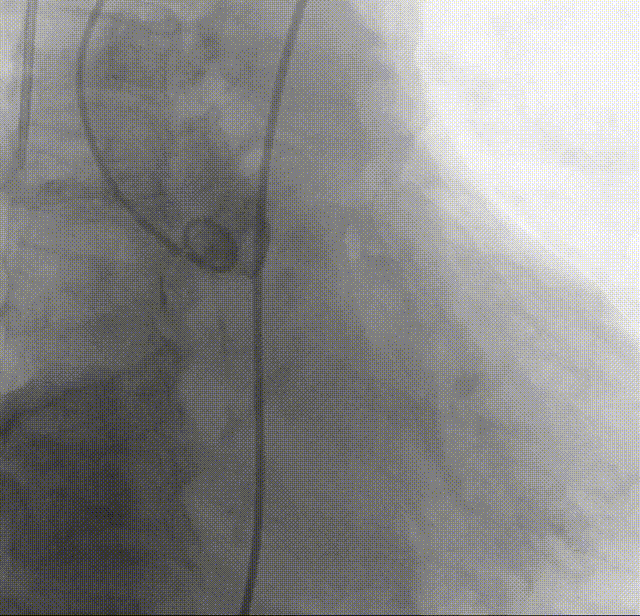

根部造影:可见开放受限,反流明显

18mm球囊预扩:可见无腰有漏,经评估决定装载TAVTF25瓣膜

瓣下1mm初始定位

瓣膜释放至全展开位

全展开位评估:锚定区呈直筒状,瓣架中段微收腰,瓣膜形态佳

打平瓣架后造影评估:瓣架形态佳,植入位置可(接近0位),可见瓣周漏,冠脉显影可